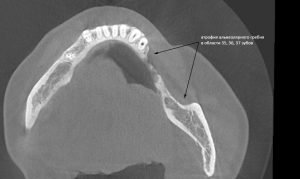

Теперь возьмём клинический случай (нижняя челюсть, отсутствия 35, 36, 37 зубов, атрофия альвеолярного гребня по ширине):

и рассмотрим его через парадигму методологического редукционизма. Или, если хотите, сквозь Бритву Оккама.

Мы имеем относительно небольшой дефект, не позволяющий, однако, установить имплантаты правильного размера в правильное положение. И два варианта остеопластической операции, НКР и АТККФ.